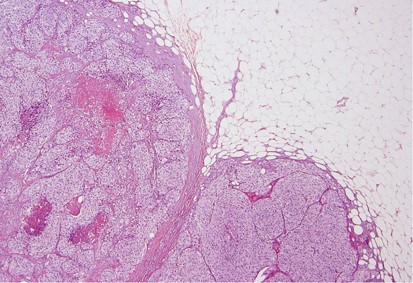

Glass slides were available for review in 53 out of 85 (62%) cases. These slides included 28 core biopsies and 30 excisions (5 cases with both cores and excisions). Seven cases involved lymph nodes only (6 axillary and 1 intramammary). The remaining 46 cases all involved the breast. Mammary lymphatic only involvement, without stromal invasion, occurred in 7% (3/46) of the cases. Certain recurrent histological features were identified, including a well-circumscribed nodule (74%, 34/46), often surrounded by a fibrous pseudocapsule (52%, 24/46) with varying thickness (Figure 1) and absence of an in situ mammary carcinoma. Interestingly, in the great majority of the tumors, lymphovascular invasion was notably absent (87%, 40/46). Tumoral calcifications were observed in non-mammary metastases of serous carcinoma type that were psammomatous in nature (75%, 6/8) (Figure 2), including two cases that involved lymph nodes.

Immunohistochemistry was used in the initial work-up of 38 (45%, 38/85) cases. In all of these cases, the primary tumors were known, except for one case in which a patient had a choriocarcinoma that had yet to be detected. Melanoma was the most frequent tumor stained (9/85), followed by lung (6/85). The most frequently used antibodies included ER, PR, AE1:AE3, S100, and TTF-1. Diagnostic errors occurred in 10 cases (12%, 10/85), the majority of these being ovarian high-grade serous carcinoma (60%, 6/10) (Figure 3). In three of the patients with ovarian cancer who were misdiagnosed as a primary breast carcinoma, the biopsy was initially misinterpreted at an outside institution. After a full clinical work-up was performed at MSKCC, the ovarian primaries were discovered and this information was then communicated to the pathologist and the diagnoses were subsequently amended. In the cases of the remaining three patients with ovarian cancer, the patients were initially treated at another institution and the history of the ovarian primaries was not immediately available. After this history was revealed, the previous material was obtained and compared to the breast/axillary lesion, resulting in a correct diagnosis. The patients with melanoma and lung primaries were misdiagnosed, again, due to the failure of the clinician to communicate the history of a prior malignancy. After this information was relayed to the pathologist, the diagnoses were subsequently changed. In the remaining two cases, the primary tumors, medullary thyroid carcinoma (Figure 4) and hepatic carcinoid tumor (Figure 5) had yet to be discovered. After a full clinical work-up, the thyroid and liver lesions were found and compared to the metastatic tumors. In addition, immunohistochemical stains were performed on the metastases, which helped to render the correct diagnoses.